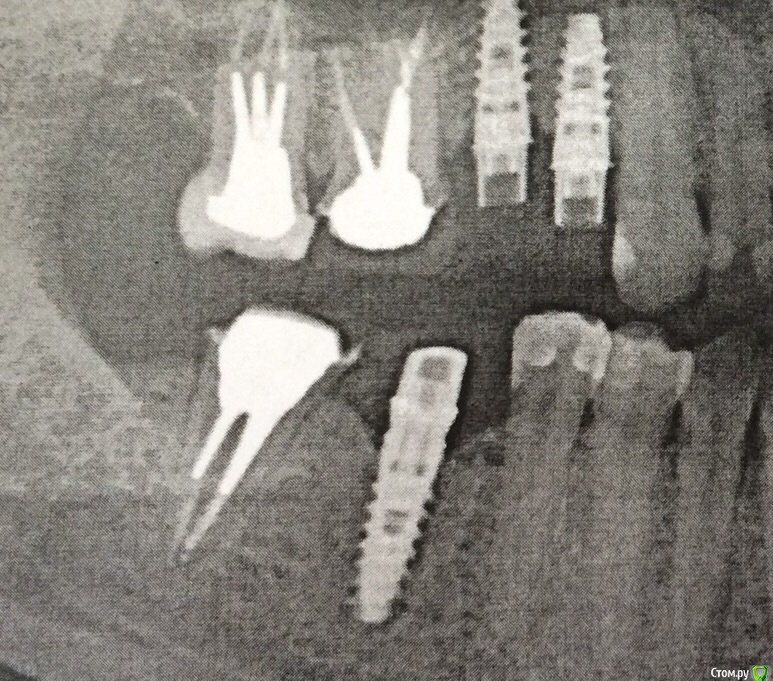

SDC Опубликовано 14 февраля, 2015 Поделиться Опубликовано 14 февраля, 2015 Для того, чтобы ответить на первую часть вопроса, нужно предоставить фото до пластики.Для того, чтобы ответить на вторую часть вопроса необходимо предоставить рентгеновский снимок. Ссылка на комментарий

SDC Опубликовано 14 февраля, 2015 Поделиться Опубликовано 14 февраля, 2015 Не слишком ли высоко десна наращена? Что Вы имеете ввиду под высоко? Выбухание слизистой в преддверии? Там пластика не проводится и не нужна.В Вашем случае необходимо увеличивать объем мягких тканей в области шеек коронок. И помочь в этом может только одна донорская зона - бугор в.ч. - слишком велика горизонтальная и вертикальная атрофия альвеолярного отростка, где установлены имплантаты.С учетом положения платформ имплантатов, формы временных коронок, атрофии кости мне кажется, что потенциала для роста сосочка недостаточно. Ссылка на комментарий

Bier Опубликовано 14 февраля, 2015 Поделиться Опубликовано 14 февраля, 2015 сосочка тут не будет. Имплантаты стоят довольно близко друг к другу. Можно еще увеличить объем тканей, будет лучше, но длинного десневого сосочка не получите. 1 Ссылка на комментарий

Nadiakroha Опубликовано 16 февраля, 2015 Автор Поделиться Опубликовано 16 февраля, 2015 (изменено) Надежда, Вам следует знать, что имплантат - это не зуб и получить такой же длинный сосочек на имплантатах, скорее чудо и редкая удача, чем ожидаемый результат. кажется мне, поправьте, если что, хирургу бы импланты потоньше или поменьше бы поставить, может и лучше б было? Изменено 16 февраля, 2015 пользователем Nadiakroha Ссылка на комментарий

Bier Опубликовано 16 февраля, 2015 Поделиться Опубликовано 16 февраля, 2015 кажется мне, поправьте, если что, хирургу бы импланты потоньше или поменьше бы поставить, может и лучше бимплантаты имеют определенный минимальный размер. Возможно надо было поставить 1 имплантат, как тут:http://img-fotki.yandex.ru/get/9319/40752090.6/0_c8c1b_ce110b67_orig.jpg http://img-fotki.yandex.ru/get/9172/40752090.6/0_c8c1c_8eb1afb1_orig.jpg Ссылка на комментарий